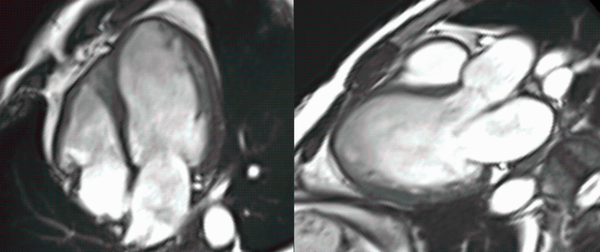

CMR strain assessment